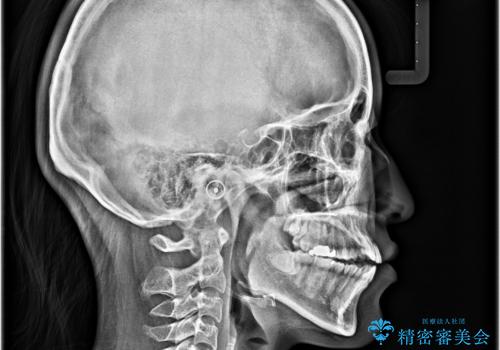

- 前歯の開咬を気にして来院された患者様です。

開咬の治療は、前歯を閉じるように動かすとともに、上下臼歯を圧下(骨内にめり込ませる)させることで進めて行きます。

インビザラインは臼歯の圧下を効果的に行えるため、インビザラインを用いて矯正治療を行うこととしました。